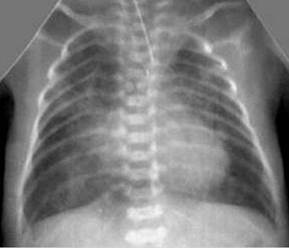

Nearly all pulmonary diseases involve the interstitium to some degree making this the ____ ____ and ____ ____ lung pattern. DX of an unstructured interstitial pattern usually is made after ______ of other patterns.

MOST COMMON

LEAST SPECIFIC

elimination

Interstital lung patterns have been described as “____ ____” because the margins of the intrathoracic structues (pulmonary vessels, cardiac silhouette, diaphram, causeal vena cava) remain visible, but are ____ _____. Similar to looking at the lungs through “ground glass” or bathroom glass.

Dirty lungs

less distinct

Radiographic findings with generalized interstital lung patterns are?`

Diffuse increase in lung opacity (“dirty lungs”)

pulmonary vessels remain visible, but margins are indistinct

Cardiac and diaphragm borders are visible

Increased interstital markings (reticular or lacey pattern of lines)

No patches of soft tissue opacity caused by alveolar filling